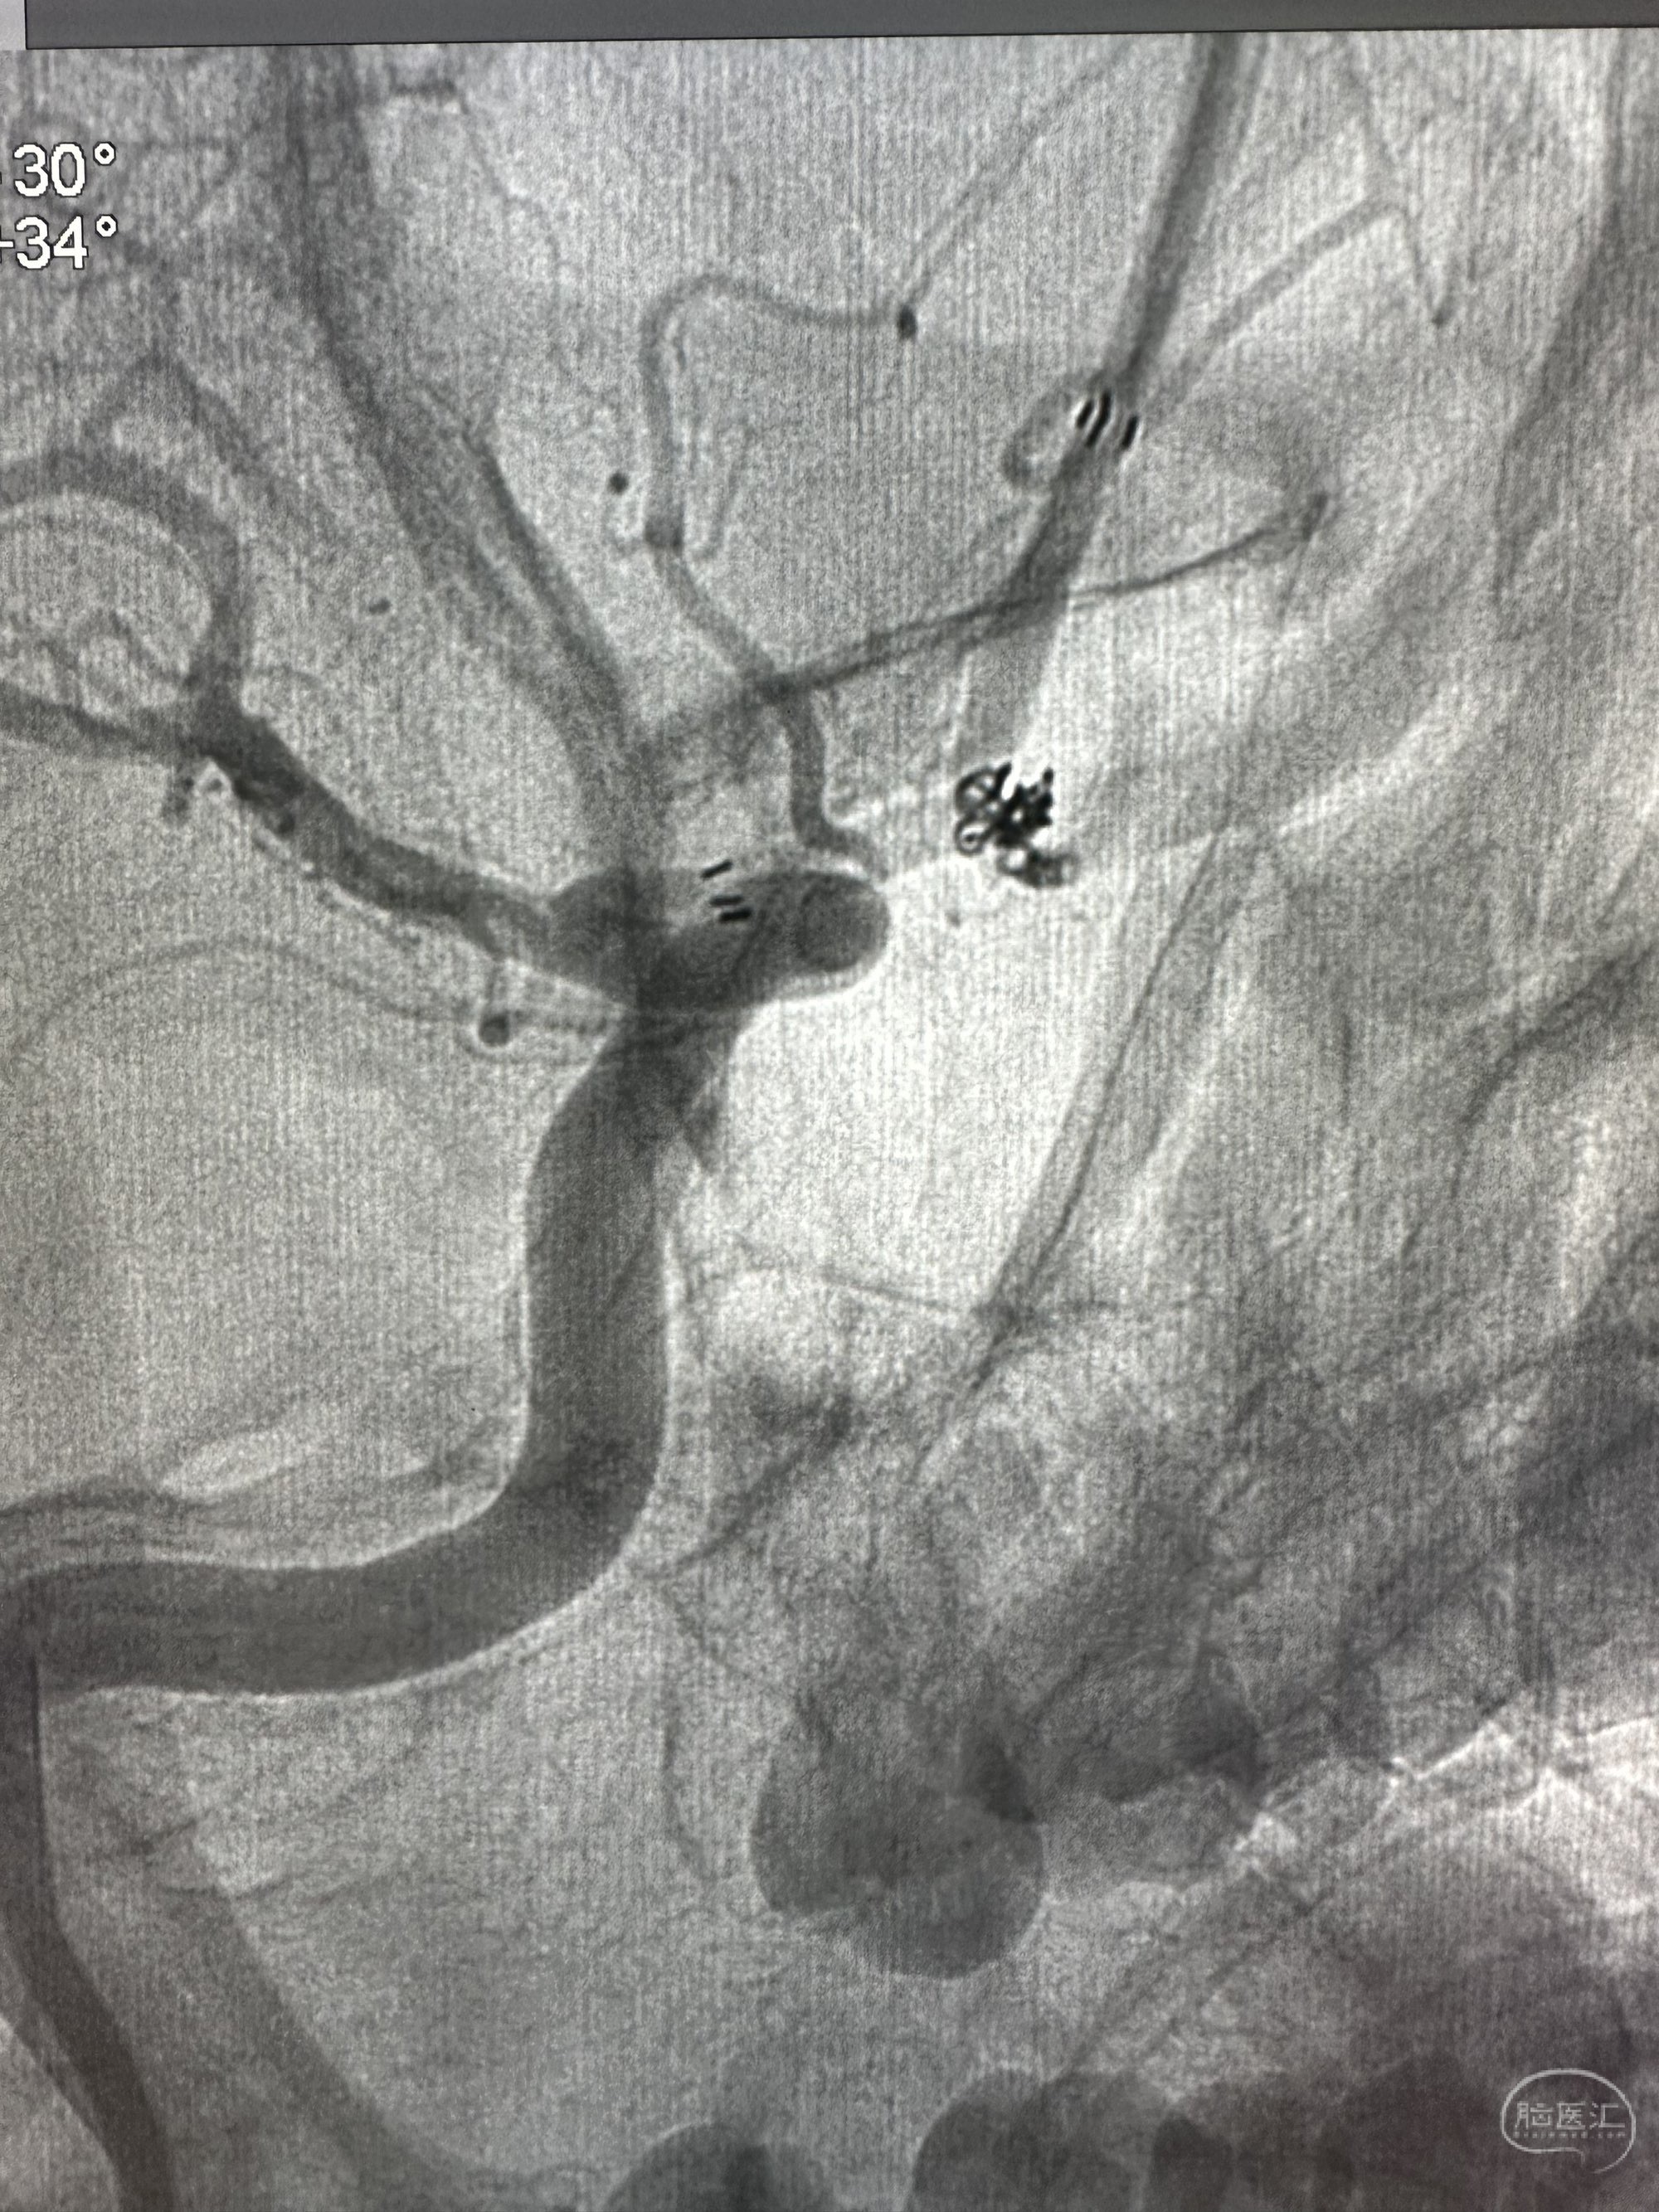

Plus支架导管到位,enchon 10直头小心接近动脉瘤,动脉瘤显影不太好

微导管到位后

第一枚圈填塞后,换了一个角度造影发现有点出血

补了一个圈,同时释放EP 2支架4*21的支架

再次造影未见出血,准备撤出微导管的时候,一个圈跑出来了,但是还是稳得住

果断再次补了一个圈